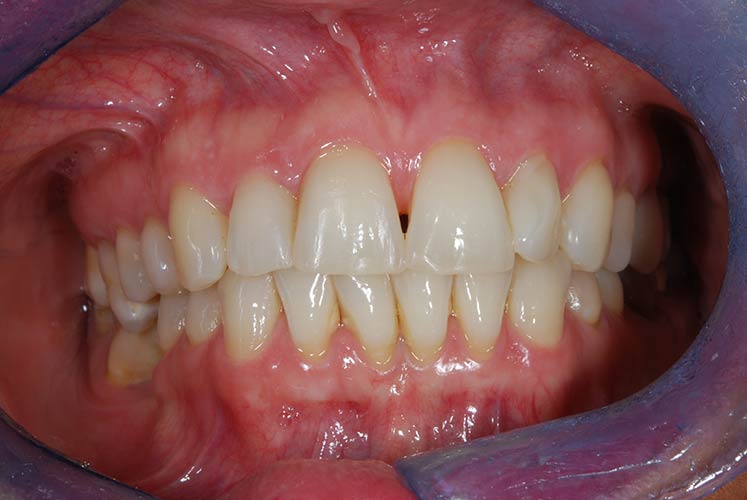

Riabilitazione gnatologica, ortodontica ed estetica

Durata del trattamento: un anno